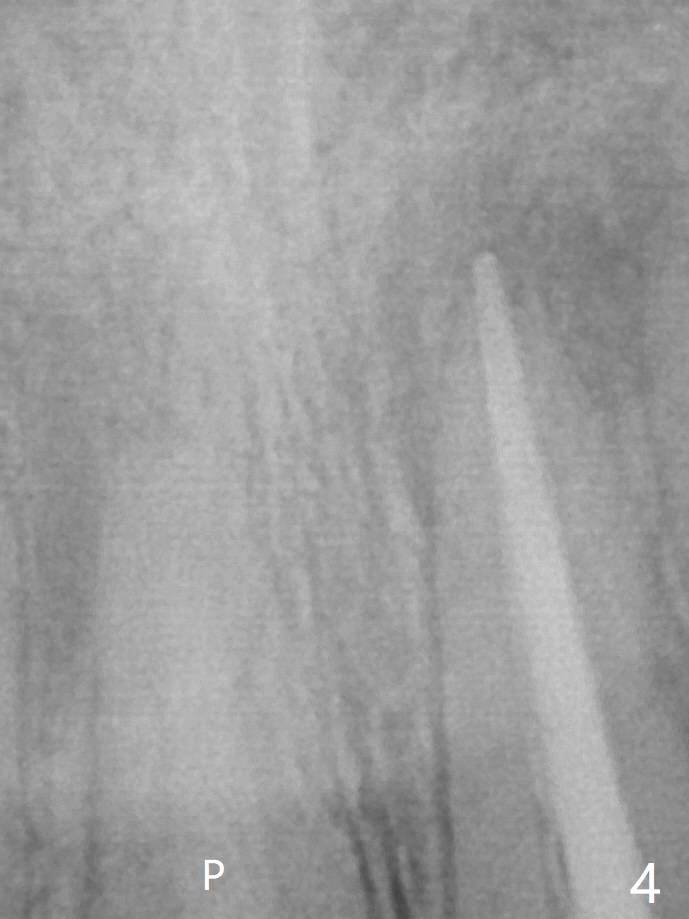

P: 氢氧化钙糊剂。术后一个月,右上1根尖没有触痛,而左上1仍有,置换糊剂后拍摄根尖片显示右上1根尖阴影仍旧很大(图五),什么时候完成永久性根管充填?